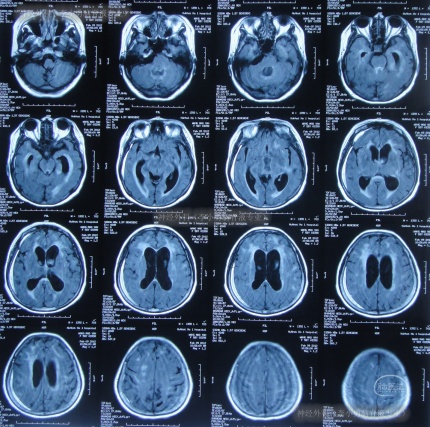

又过2月后即2011年10月14日,夜里2点起夜时突然站不稳,再次出现头昏,呕吐频繁,四肢无力,2011年10月17日第2次就诊于第2家医院:呼和浩特市某医院神经内科住院治疗,行头颅MRI(图-1)认为“末梢神经脱髓鞘病变,考虑为格林巴利综合征,轻度脑积水”。

图-1:2011年11月17日头颅核磁